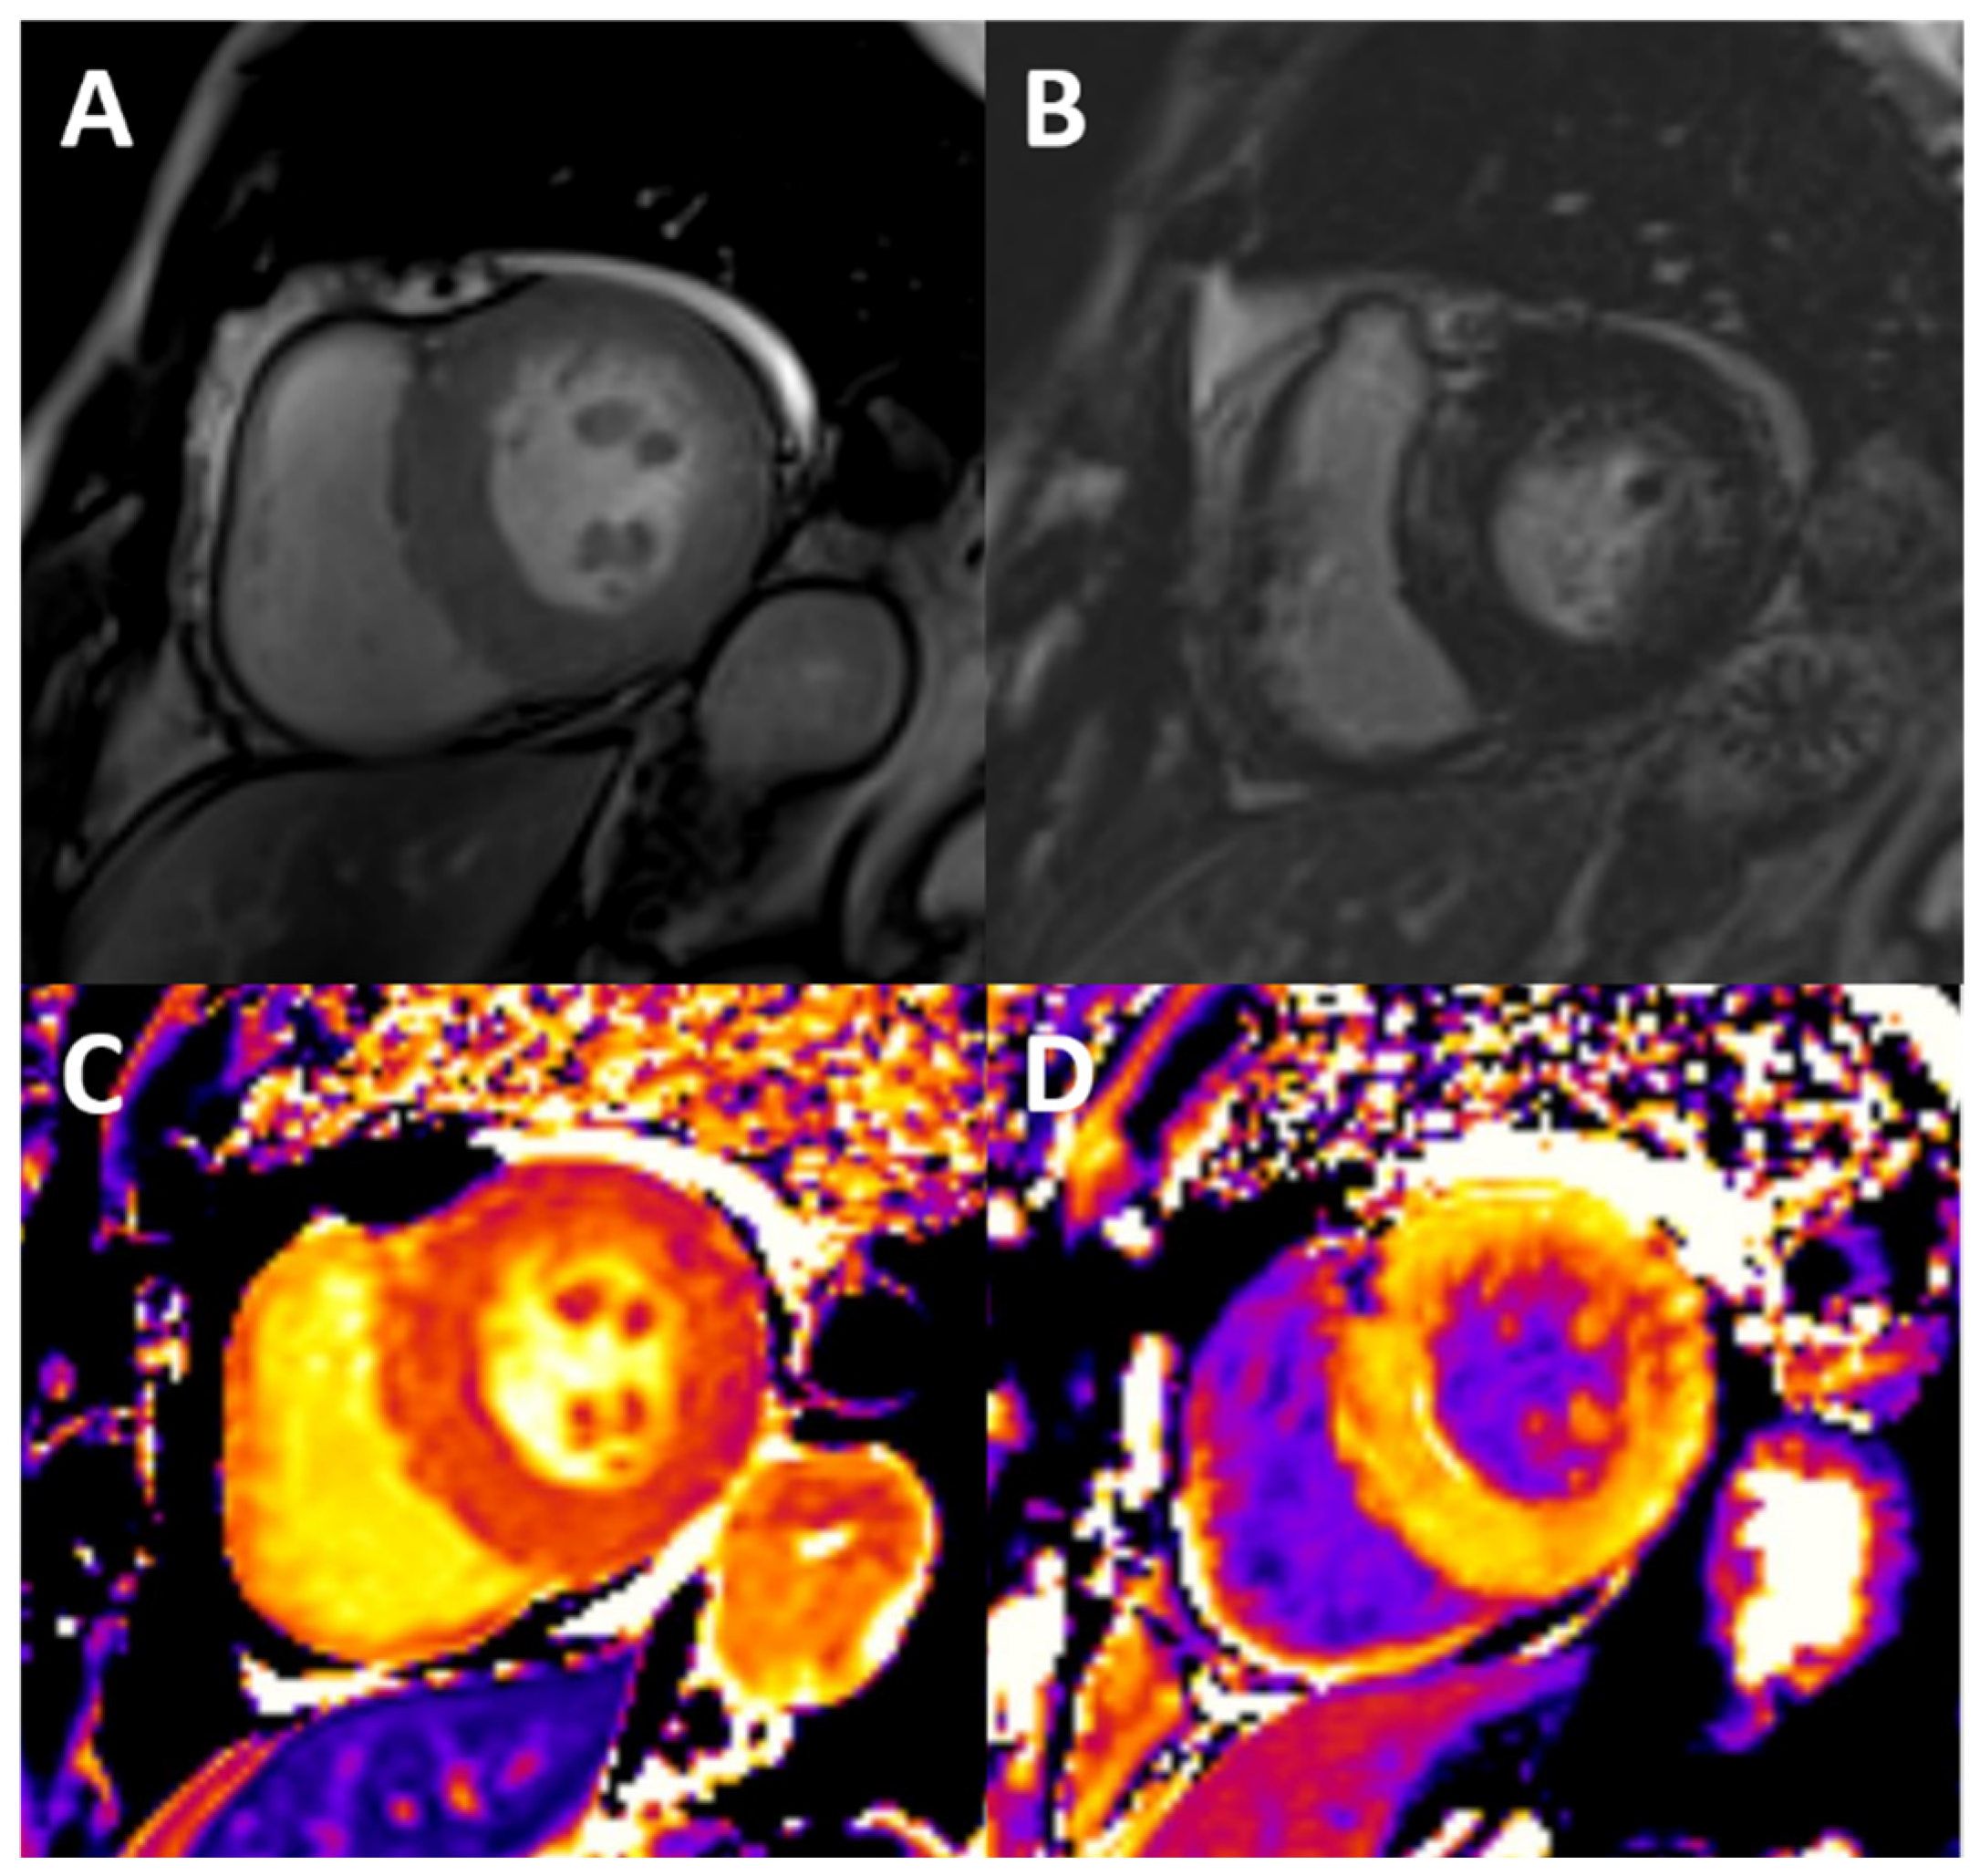

3.3. Diffuse Fibrosis and Edema

3.4. Vascular Stiffness

- Arcari, L.; Camastra, G.; Ciolina, F.; Danti, M.; Cacciotti, L. T1 and T2 Mapping in Uremic Cardiomyopathy: An Update. Card. Fail. Rev. 2022, 8, e02. [Google Scholar] [CrossRef]

| Fibrosis | + | Backscatter echocardiography | No | ++++ | T1 mapping; LGE. | Yes | + | CT ECV | No | [16,17,18,19,20,21,22,23,24,25,26,27,28,29,30,31,32] |

| Edema | - | - | - | ++++ | T1 and T2 mapping | No | - | - | - | [16,24,25,26,28,29,30] |

| Vascular stiffness | + | Tissue Doppler; speckle tracking | No | +++ | Phase-contrast imaging | No | ++ | Vascular calcification (indirect estimate) | Yes | [15,23,45,64,65] |